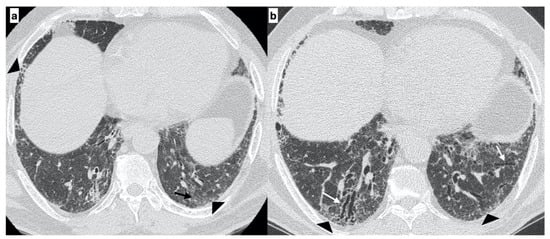

At diagnosis, there was a statistically significant difference in the HRTC pattern between the two groups: sporadic IPF patients had a predominantly typical UIP pattern compared to familial IPF patients (60.0% vs. 21.1%, respectively). There was a predominance of an alternative diagnosis HRTC pattern in familial IPF compared to sporadic IPF (31.6% vs. 2.2%, respectively) (see Figure 1, Figure 2 and Figure 3). The HRCT for 6/19 patients with a familial pulmonary fibrosis at the onset of symptoms had an alternative diagnosis pattern: this was due to the presence of a fibrotic nonspecific interstitial pneumonia (NSIP) pattern in 4/19 patients, whilst in 2/19 patients it was due to the presence of honeycombing with upper-mid lung distribution (see Figure 1). At the onset of symptoms, only 1/46 sporadic IPF patients had an alternative diagnosis HRCT pattern, due to the presence of honeycombing with upper-mid lung prevalence and mosaic attenuation; the definitive diagnosis of IPF was made by biopsy (see Figure 2 and Figure 4). After 2 years from diagnosis in the familial IPF group, we observed a slight increase in the typical UIP pattern at HRTC evaluation (see Figure 3 and Figure 5).

Figure 4. A 67-year-old male with “UIP pattern” on HRCT at the onset of respiratory symptoms. Axial HRCT plane shows honeycombing (black arrows) and reticulations (arrowheads) with a basal predominant distribution (a); traction bronchiectasis (white arrows) and distribution of alterations are better visible on the sagittal plane (b). Genetic analysis demonstrated the following types of mutations: SFTPA2, promoter-TERT, TERT.